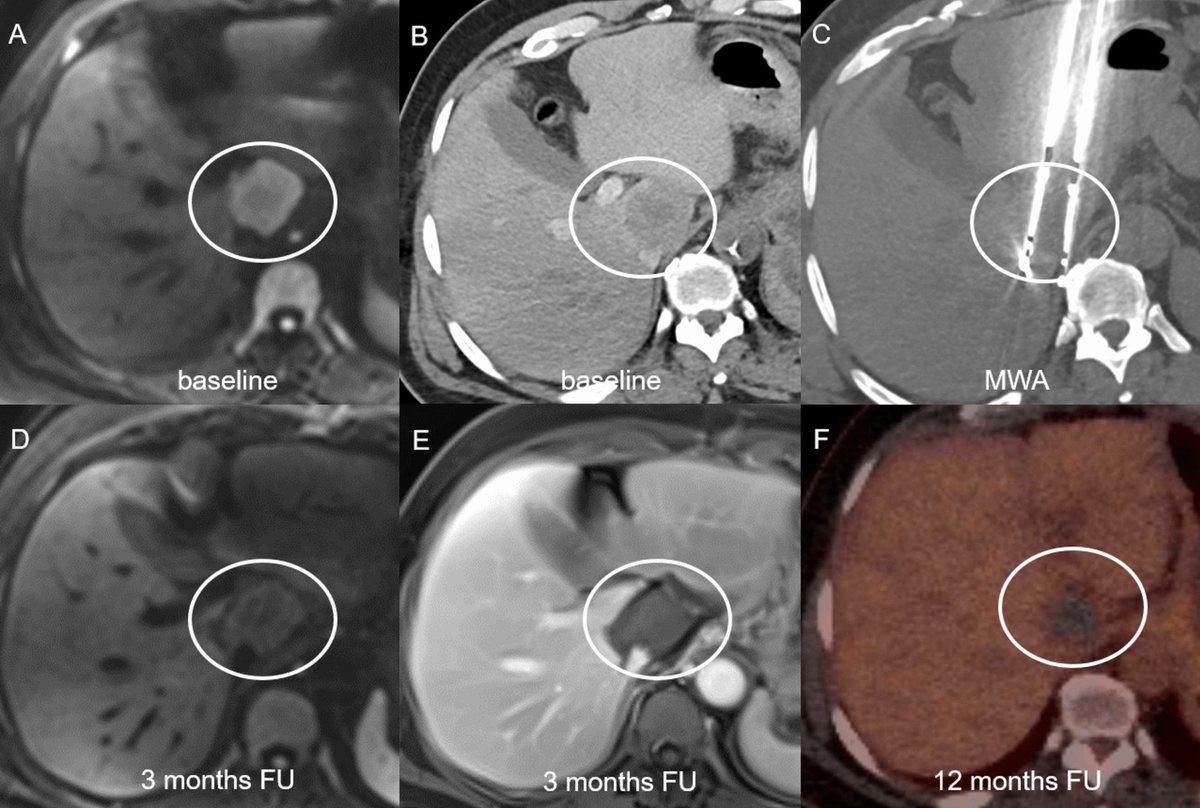

MARGIN: Randomized Trial of Arterial CT Portography Versus Standard Imaging Guidance for Percutaneous Thermal Ablation of Colorectal Liver Metastases